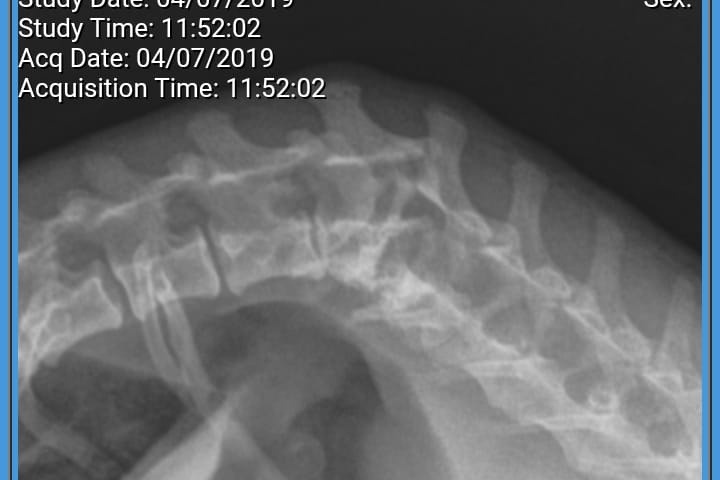

After we picked her up we took her to our vet for xrays, and that's when we saw the horrible fracture in her back. It was an old fracture that was never treated, which caused her the inability to walk with her back legs. However, she could stand up enough to somewhat drag them. With acupuncture and chiropractic treatments she was able to start walking better, but over the months the fracture has worsened and she's now mostly dragging back legs and becoming more arthritic. Our Veterinarian says it will be helpful now to stabilize the back so she won't become paralyzed and lose her ability to go potty on her own.